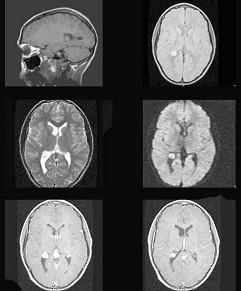

问题 有关脑室内脑膜瘤(如图所示),下列哪项说法不恰当()

选项 A.起始于脉络丛 B.侧脑室内脑膜瘤多位于侧脑室三角部 C.临床常见头痛、视乳头水肿 D.三、四脑室内脑膜瘤可引起梗阻性脑积水 E.脑血管造影显示侧脑室内脑膜瘤供血动脉多为大脑中动脉

答案 E